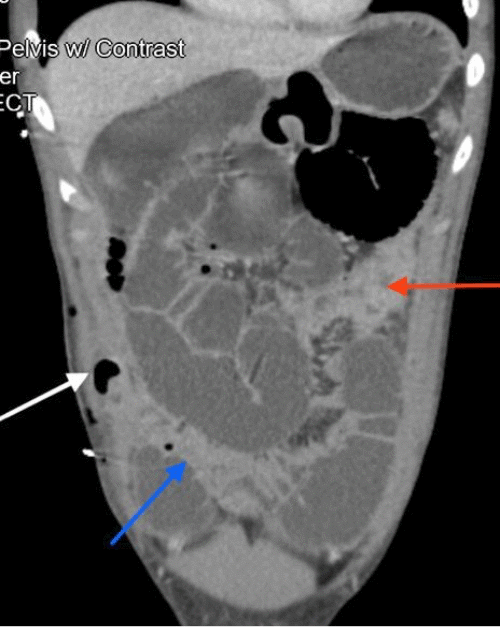

Contrast-enhanced CT scan of the abdomen and pelvis revealed findings consistent with mechanical obstruction. A transition point abutting the abdominal wall at the prior projectile injury site was noted proximal to the ileocolic anastomosis (Figure 3). A small bowel follow-through demonstrated small amounts of contrast in the distal small bowel loops at an 8-hour delay, indicating possible incomplete obstruction (Figure 4). Following discussion with the patient and guardian, a decision was made to perform a re-exploratory laparotomy.

Figure 3. CT Depicting Mechanical Small Bowel Obstruction at Prior Injury Site. Published with Permission

Axial view demonstrating the transition point abutting the fascial defect in the abdominal wall

(B) Axial view showing the collapsed bowel originating proximal to the ileocolic anastomosis (blue arrow)

(C) Axial view  of the ileocolic anastomosis (green arrow)

(D) Sagittal view of the ileocolic anastomosis (green arrow)

(E) Axial views showing collapsed bowel located distal to the anastomosis

(F) Axial view showing collapsed bowel located proximal to the anastomosis